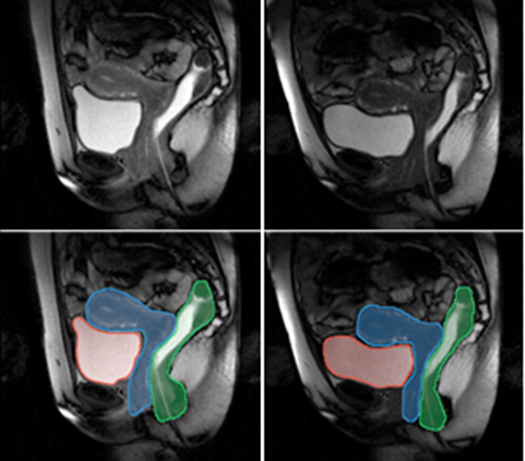

Examples of segmentation of the main pelvic organs at the beginning (left) and end (right) of a push-out exercise.

Semi-automatic segmentation of the major pelvic organs on a 2D dynamic MRI sequence.